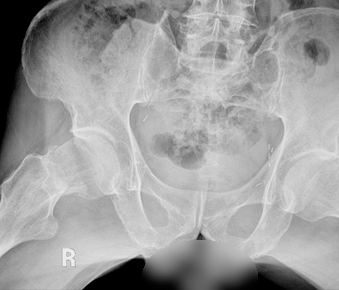

수술 전 후 방사선 사진

수술 전

• 고관절골절_수술 전

화살표